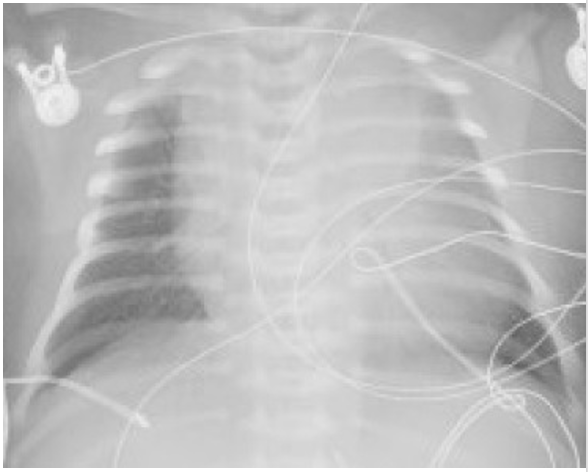

You order a blood gas test and a chest x-ray. The neonate’s x-ray is shown here. What is the pathophysiology of the most likely diagnosis?